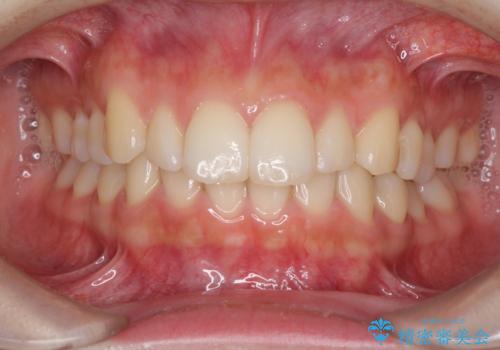

気になる前歯を治したい 短期間でのインビザライン矯正

担当医 藤巻太一朗